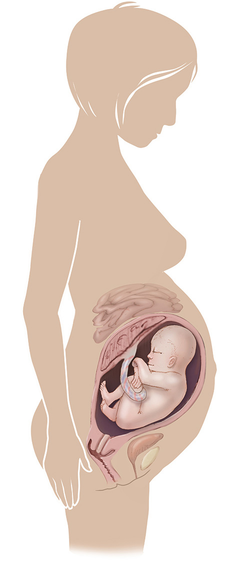

مراحل تطور الجنين أثناء الحمل

تطور الجنين خلال فترة الحمل على ثلاثة مراحل: أول 14 أسبوع من الحمل ، ثم تطوره بداية من الأسبوع 14 وحتى 28 أسبوعا ، ثم الثلث الأخير من 28 إلى 40 أسبوع من الحمل ... المزيد

مراحل تطور الحمل أسبوعيا بالصور

مراحل تطور الحمل أسبوعيا لكل من الأم والجنين داخل الرحم مدعومة بالصور التوضيحية ... المزيد